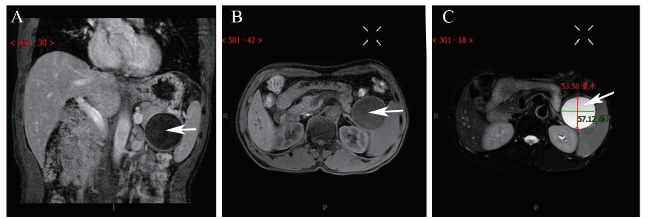

1个月后患者返院复查腹部MRI,胰腺尾部见类圆形T1WI低信号影,T2WI高信号影,DWI呈稍高信号,内壁光滑,增强扫描未见强化,考虑胰腺尾部囊性占位,良性病变以假性囊肿可能性大(图3)。患者为进一步治疗,入住我院肝胆外科,有手术指征并与患者及家属沟通后于全身麻醉下行腹腔镜胰体尾切除术+脾切除术+腹腔粘连松解,术中见胰尾处有一大小7.0 cm×8.0 cm的囊性肿物,包膜完整,质韧,活动度可,肿物与脾动静脉、主胰管间距约0.5 cm以上,其余胰腺部分质地软,胰腺周围、脾动脉淋巴结及脾门淋巴结部分未见肿大。术后病理结果:囊壁由纤维组织构成,内壁大部分区域未见被覆上皮,局部被覆鳞状上皮,囊壁内见较多淋巴细胞浸润,局部淋巴滤泡形成(图4)。最后诊断为PLEC。

图3 一例PLEC患者腹部MRI图

注:A为MRI平扫冠状位图片,胰腺尾部见类圆形T1WI低信号影,T2WI高信号影,DWI呈稍高信号,内壁光滑;B为MRI平扫横断位图片;C为MRI增强扫描横断位图片,未见强化;白色箭头所示为低密度影。